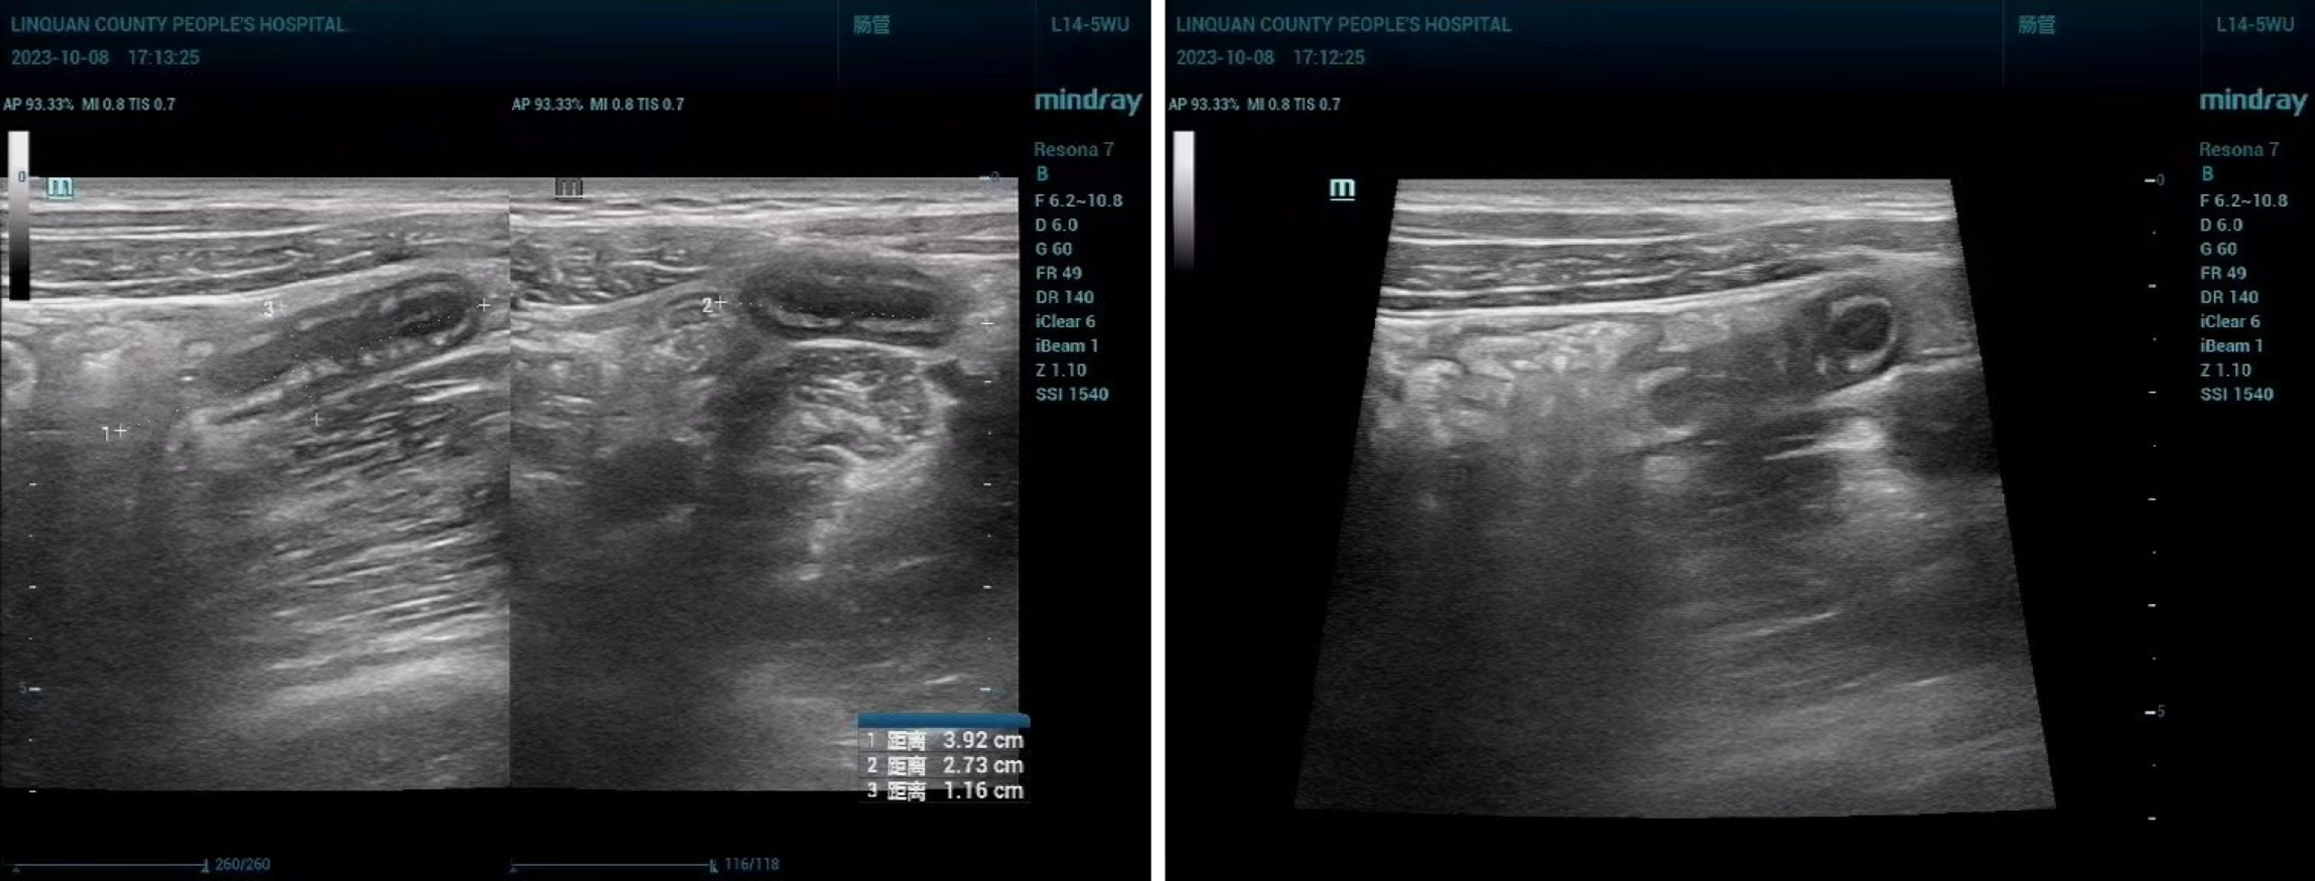

Outcome indicators: (1) Diagnostic efficiency of two ultrasonography methods: Taking surgical pathology as the diagnostic gold standard, we compared the diagnostic efficacy (sensitivity, specificity, accuracy, positive and negative predictive value) of conventional abdominal ultrasonography and transabdominal superficial ultrasonography (TASU) in the diagnosis of acute appendicitis. Judgment basis[8]: The pathological examination results showed appendiceal swelling and conjunctival congestion, accompanied by exudate and neutrophil infiltration, while an effusion could be observed in the appendiceal cavity in some patients. Abdominal ultrasonography showed the following: An enlarged appendix; the lumen had expanded and the wall thickness had increased; appendiceal cavity occlusion or a stercoral shadow was visible; the appendix had cystic mass and was accompanied by fluid collection; (2) Comparison of the diagnostic efficacy of the two ultrasonography methods (see Figure 2): The surgical and pathological results were set as the gold standard, and the diagnostic efficacy of conventional abdominal ultrasonography and TASU for acute simple appendicitis was compared. Judgment basis: Pathological examination findings showed a mild swelling of the appendix, and the lesion could be seen only in the mucosa and its underlying layers, accompanied by neutrophil infiltration. Abdominal ultrasonography showed a clear image boundary, which was difficult to distinguish from the normal tissue. The appendix was significantly thickened, with a thickened mucosa. The transverse lumen showed “concentric circles”, and the longitudinal section was “sausage-like”; (3) Comparison of the diagnostic efficacy of the two ultrasonography methods: Surgical pathology was set as the gold standard for diagnosis, and the diagnostic efficacy of conventional abdominal ultrasonography and TASU was compared for acute suppurative appendicitis. Judgment basis: Pathological examination showed an obvious swelling of the appendix, serosal congestion, pus extravasation, muscular layer and serosal layer involvement, and fluid accumulation in the appendiceal cavity. Abdominal ultrasonography showed that the appendix had become thick, and the definition of the boundary with the normal tissue was reduced. A cystic hypoecho with an irregular shape could be observed, and the echo inside the lesion was dense and distributed in dots. The transverse lumen showed a “target ring-like”, and “rat-tail-like” shape as seen through longitudinal section; (4) Comparison of the diagnostic efficacy of the two ultrasonography methods: Setting surgical pathology as the diagnostic gold standard, we compared the diagnostic efficacy of conventional abdominal ultrasonography and TASU for diagnosing acute gangrenous appendicitis. Judgment basis: Pathological examination results showed necrosis of the appendiceal wall in a black or dark purple color, with fluid collection, increased pressure, and abnormal blood supply to the surrounding tissues in the lumen. Abdominal ultrasonography showed morphological changes and obvious swelling of the appendix. The appendiceal tube wall was thickened and indistinct in level. The echoes in the cavity were dense and distributed in dots. The liquid echo was cloudy. The surrounding tissues were obviously exuded and accompanied by adhesion; and (5) Diagnostic consistency analysis: We analyzed the diagnostic consistency of TASU and pathological examination in acute appendicitis as well as various types of acute appendicitis. The consistency was found to be poor when Kappa < 0.4, medium when 0.4 ≤ Kappa ≤ 0.75 and high when Kappa > 0.75.

TASU combines the characteristics of abdominal ultrasonography and superficial ultrasonography. The latter is primarily used for the examination of superficial organ lesions and has the advantages of high sensitivity, high safety, and easy operation. It is widely used for the diagnosis of diseases such as arthritis, tenosynovitis, hemangiomas, and testicular torsion. TASU uses high-frequency probes with high resolution, which can clearly display the hierarchical structure of the appendix wall and evaluate wall structure and intracavitary status. Compared with traditional abdominal ultrasonography, TASU can more accurately detect small lesions and mild inflammation, improving diagnostic accuracy[13]. The appendix is elongated and curved, with a normal length of about 7-9 cm and a lumen diameter of only 0.2 cm. When the cavity is blocked, the pressure increases, and bacteria invade: This may affect the blood supply of the appendiceal tissue, thereby inducing disease. There is no obvious swelling in the cavity in the case of acute simple appendicitis, which is characterized by thickening of the tube wall, clear boundaries, an absence of echo in the cavity, and the presence of strong echo fecal stones[14,15]. The appendix in the case of acute suppurative appendicitis is significantly swollen, with increased tension, an intracavity diameter greater than 10 mm, thickening of the wall, decreased surface smoothness, and a dense echogenicity distributed in dots, which is difficult to distinguish from surrounding tissues. The appendix wall of acute gangrenous appendicitis displays further thickening, continuous interruption, and blurred boundaries with the surrounding normal tissues. Low echo areas can be seen inside the cavity, with uneven echoes and scattered strong echoes. An echo-less mass can be seen in the lower right abdomen, accompanied by adhesions with surrounding tissues[16,17]. Compared with other imaging examinations, TASU has higher safety and real-time perfor